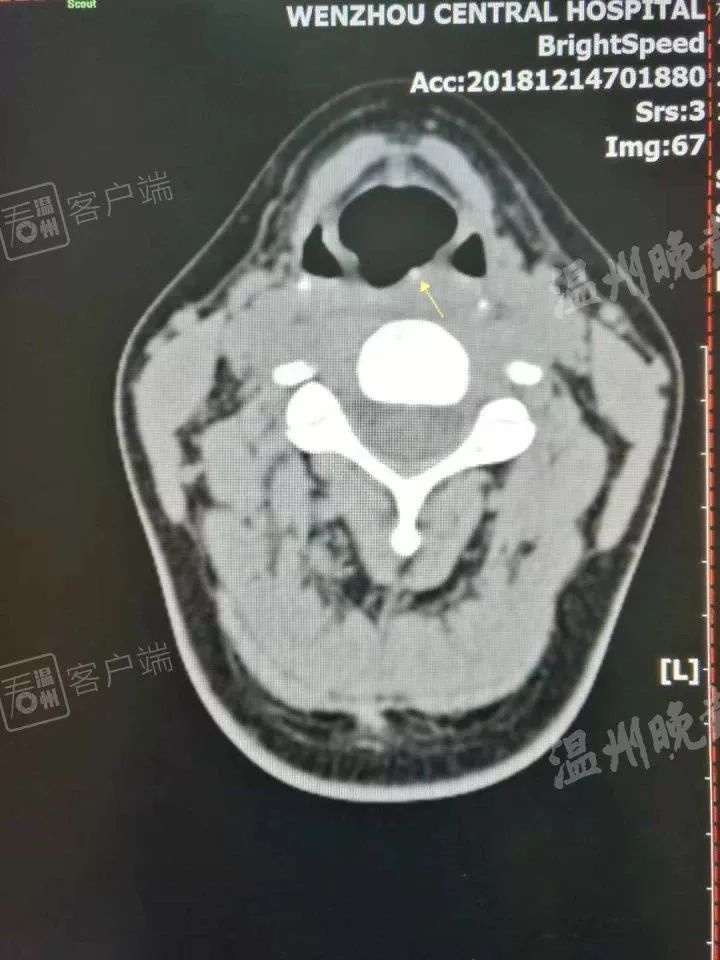

接诊的是该院耳鼻喉科医师伍淦。伍淦说,他用间接喉镜检查了一遍,也没有发现异物卡喉,后来让杨女士做了CT,这才找到刺入咽后壁(大约喉结位置)里的“暗器”。“患者必须发‘E’的音,才能通过喉镜看到‘暗器’露出的尖尖角。只要看到了,很快就取出来了。”

伍淦取出一看,原来是一根断掉的扁竹签,大约2厘米长。他猜测,应该是杨女士吃烧烤太急,把这截竹签和食物一起吞咽,结果卡住了喉咙,导致杨女士喉咙黏膜损伤肿胀。